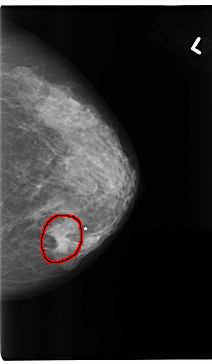

FILE: C_0175_1.LEFT_MLO.OVERLAY

TOTAL_ABNORMALITIES 1

ABNORMALITY 1

LESION_TYPE MASS SHAPE ROUND MARGINS SPICULATED

ASSESSMENT 5

SUBTLETY 5

PATHOLOGY MALIGNANT

TOTAL_OUTLINES 1

BOUNDARY